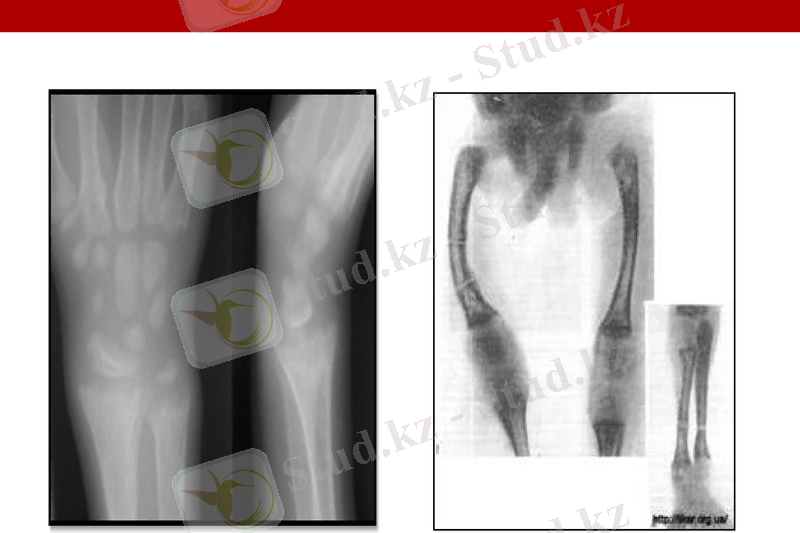

Рахитті анықтау үшін рентгенологиялық және биохимилық зерттеу әдістерін қолданады. Ең ерте байқалатын зертханалық белгі - остеобласт ферменті сілтілік фосфатазаның белсенділігінің жоғарылауы және фосфор концентрациясының төмендеуі. Рахиттың алғашқы рентгенологиялық симптомы диафиз бен эпифиз арақашықтығының ұлғаюы болып табылады. Ол метафиздің өсуі, ұзын сүйекте өсінді пайда болуы, остеопороз әсерінен өзгеріске ұшырайды. Ары қарай остеопороз ұлғаяды, метафизарлы зона көлемі өседі, әктену аймағы төмпек түрден горизонталдыға ауысады, сүйек тіні бұзылады. Аурудың асқынуы кезінде ұзын сүйектер мен “жасыл бұтақ” типі бойынша қабырғалар сынығы болуы мүмкін. Реконвалесценция кезеңінде метафизде кальций фосфаты жіңішке тығыз сызық түрінде қорға жиналады. Рахиттың рецидивті ағымында осындай бірнеше әктену сызықтары пайда болады.